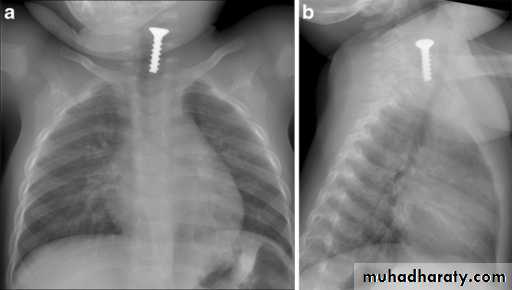

Foreign Body Inhalation

A common problem

Most common site for foreign body inhalation is?Clinical presentation:

• Asymptomatic only discovered by a witness• Stridor with dyspnea if stuck in the trachea or larynx

• wheezing with a persistent cough when in the bronchus

• repeated or persistent pneumonia with suppuration (late presentation).

Investigations:

Chest X-ray:

DDx: FB in the esophagus